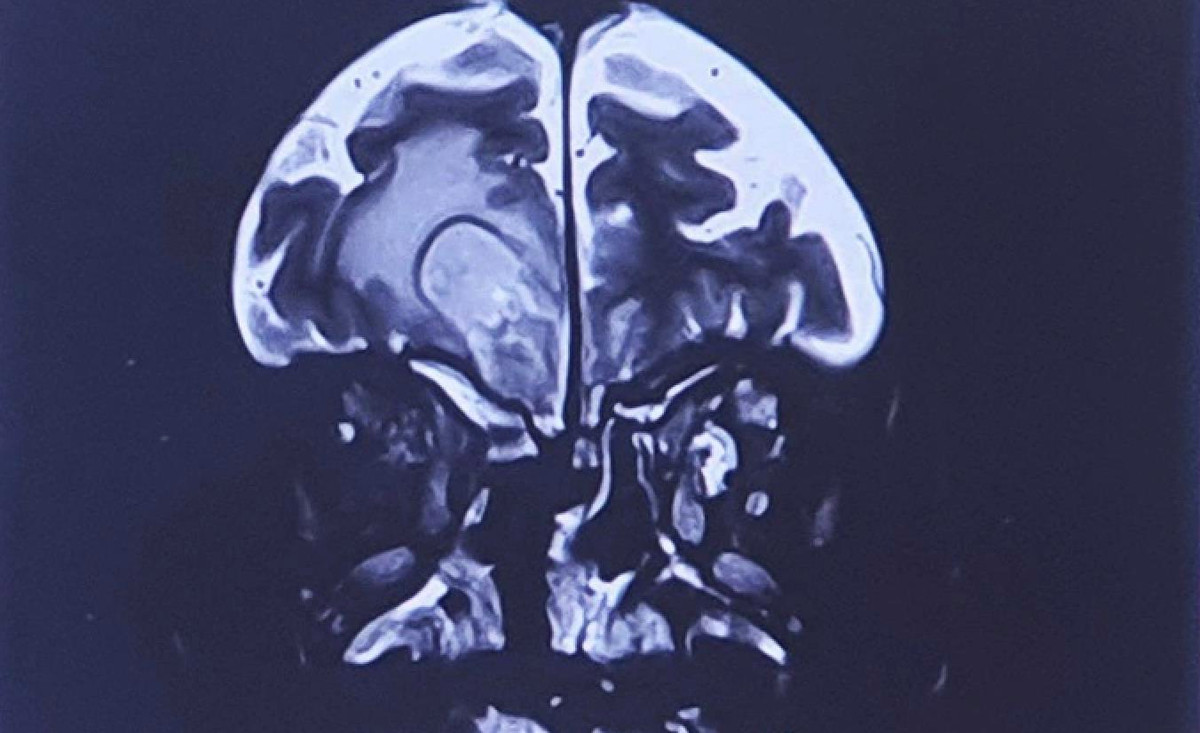

Nhiễm nấm đen gây hoại tử xương, tử vong 'hậu COVID-19': Chuyên gia nói gì?